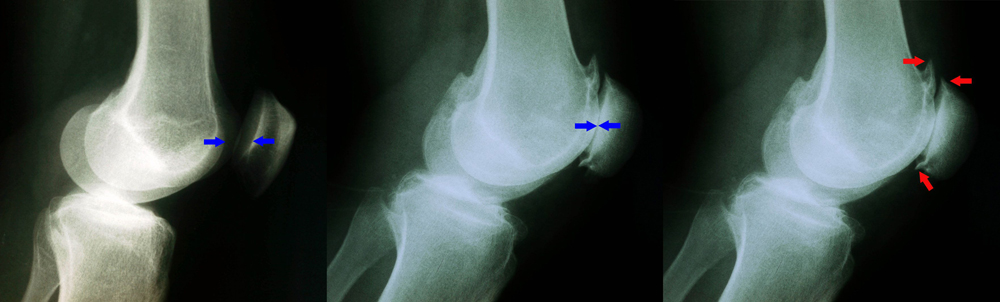

X-rays of healthy knee and knee with patellofemoral arthritis

(Left) This X-ray shows a normal knee from the side. The arrows point to the normal amount of space between the bones. (Middle) In this X-ray, the arrows point to narrowed joint space due to patellofemoral arthritis. (Right) Here, the arrows point to bone spurs that have developed due to the arthritis.

Courtesy of Stuart J. Fischer, MD, FAAOS